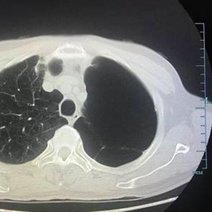

胸片怎么看

学会看胸片是临床医生必备的技能之一,首先,看胸壁的X线表现,观察胸壁软组织有大的肿块,有皮下积液、积气,同时观察肋骨的连续性是否有中断,这是肋骨骨折的X线征象...73227人收听

在临床上胸部X光片检查是常用的一种检查方法,它是利用X线产生图像,从而观察胸部的病变。胸片的观察需要按一定的顺序,一般可以按照从上往下的顺序,观察双肺上叶...1人收听